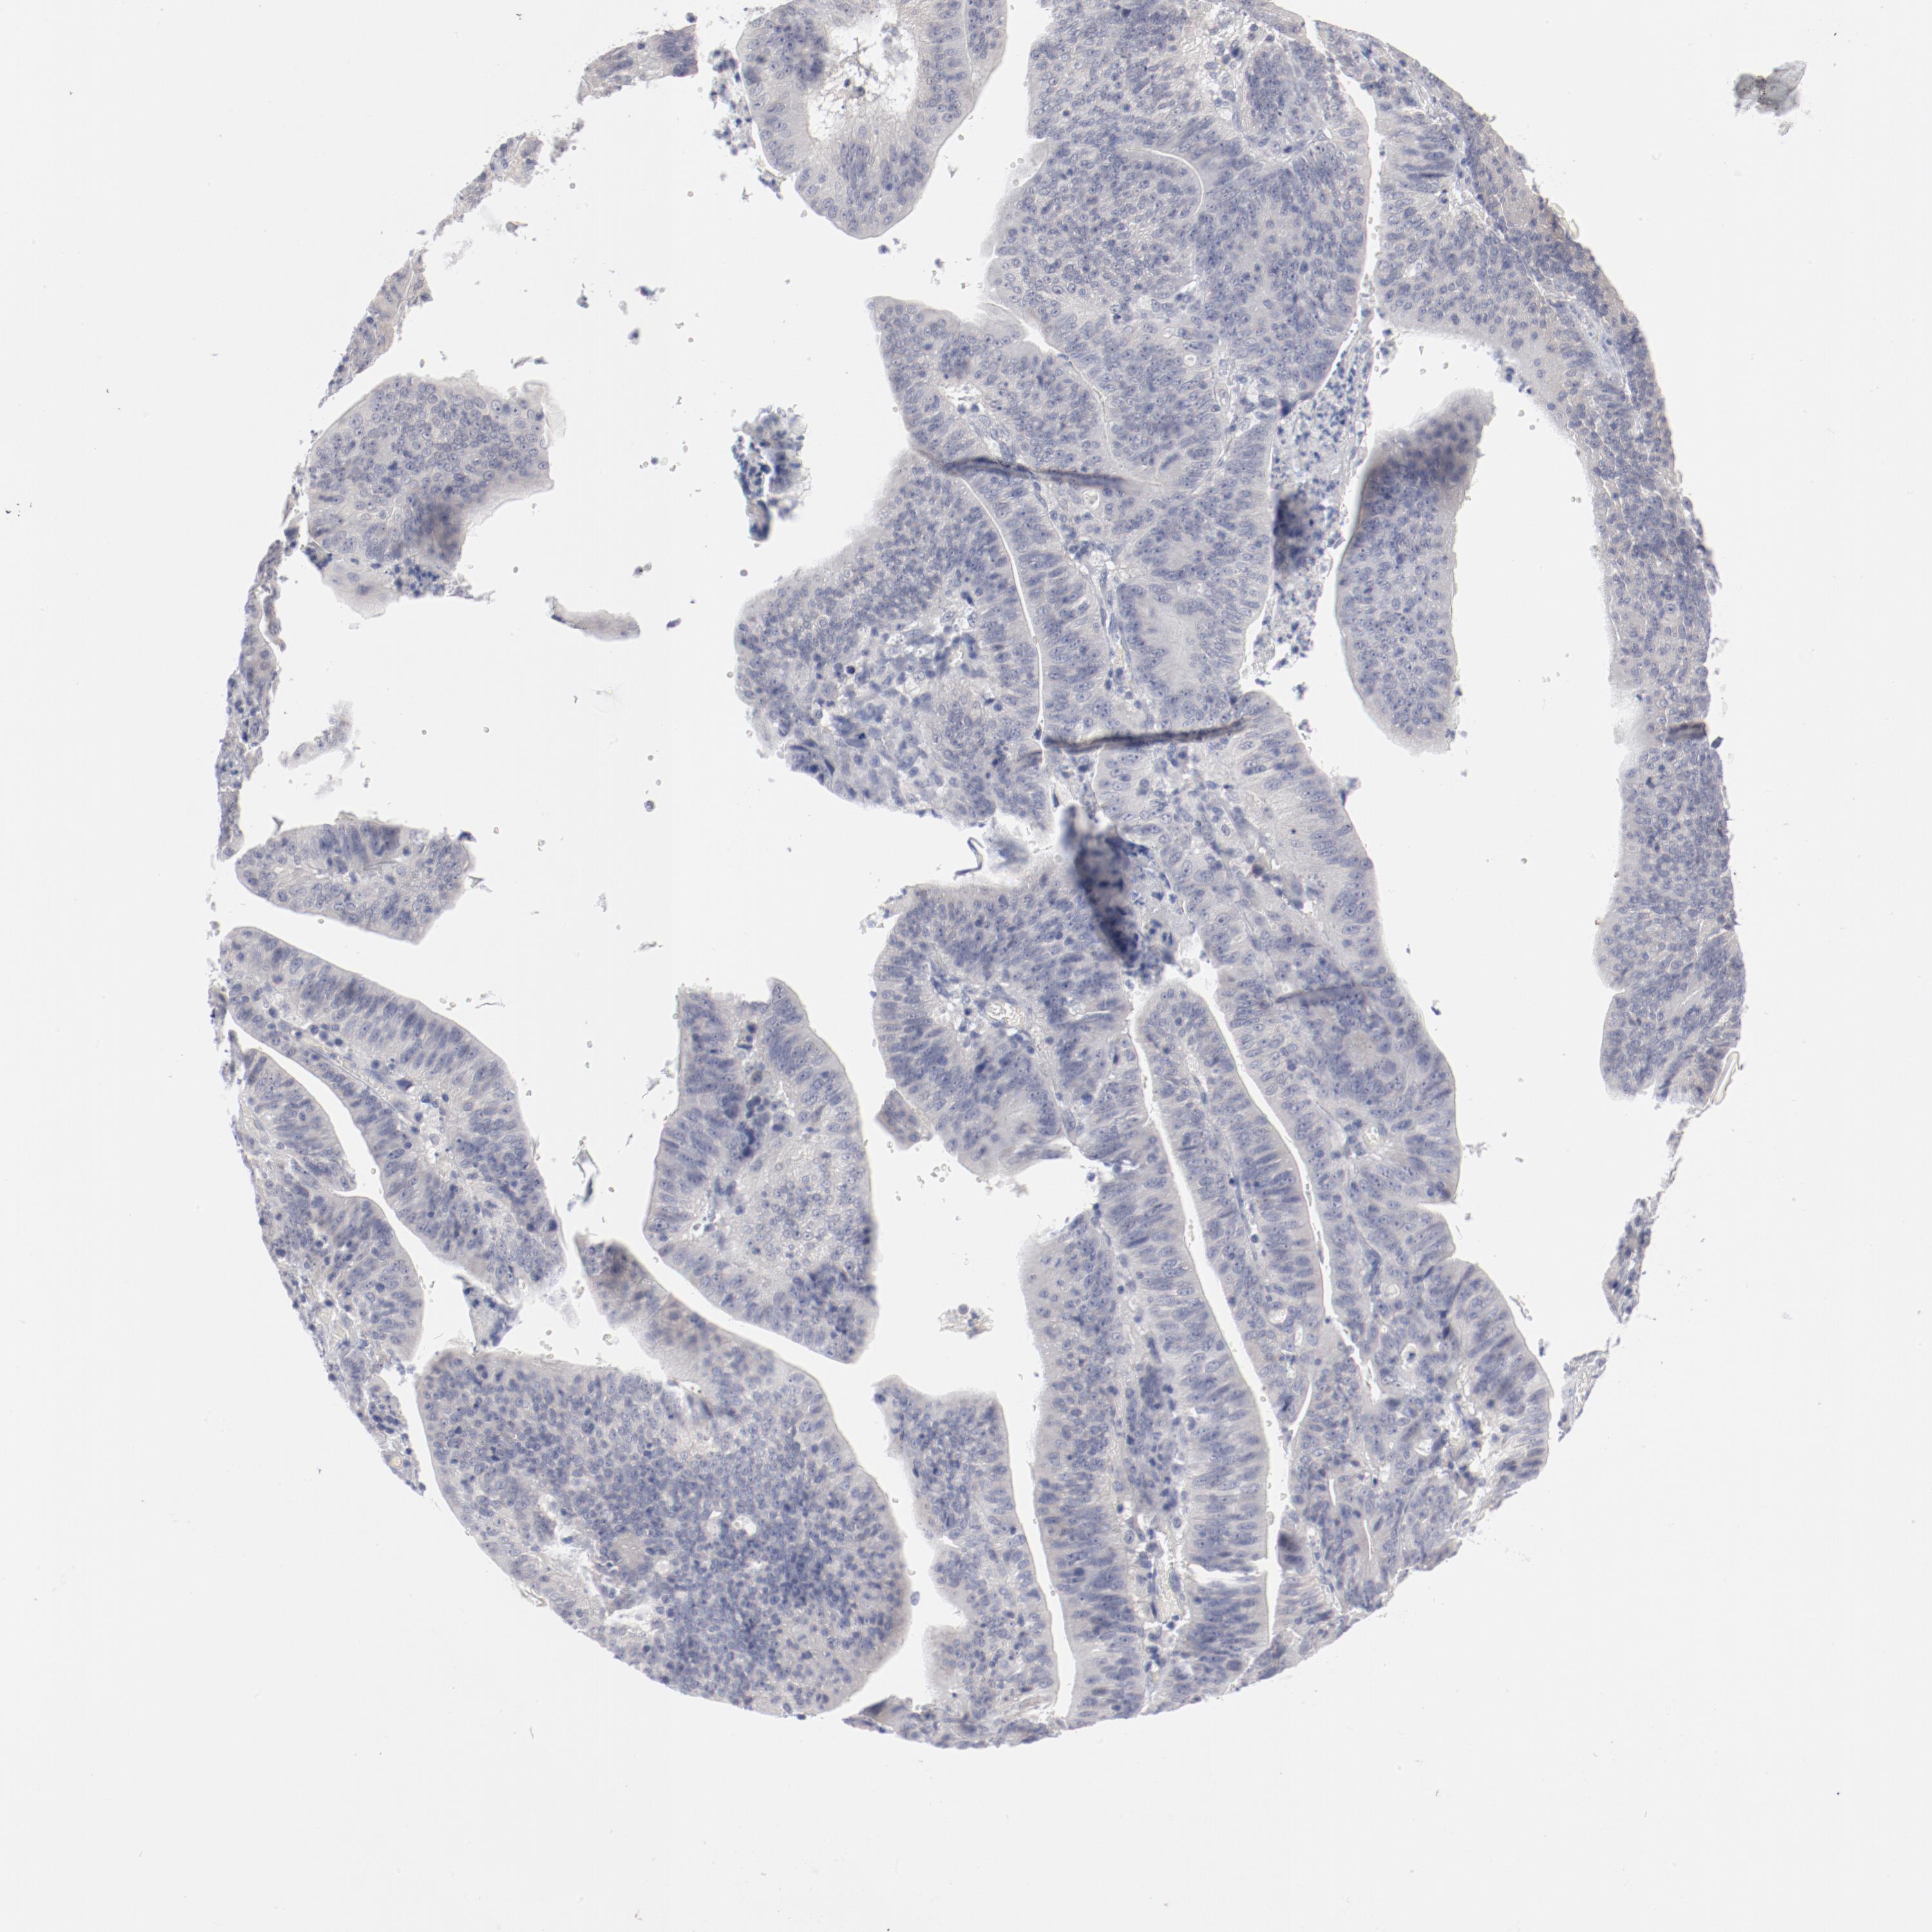

STOMACH CANCER - Protein expressioni

A mouse-over function shows sample information and annotation data. Click on an image to view it in a full screen mode. Samples can be filtered based on level of antibody staining by selecting one or several of the following categories: high, medium, low and not detected. The assay and annotation is described here.

Note that samples used for immunohistochemistry by the Human Protein Atlas do not correspond to samples in the TCGA dataset.

Antibody stainingi

Antibody staining in the annotated cell types in the current human tissue is reported as not detected, low, medium, or high, based on conventional immunohistochemistry profiling in selected tissues. This score is based on the combination of the staining intensity and fraction of stained cells.

Each image is clickable and will lead to virtual microscopy that enables deeper exploration of all samples and also displays staining intensity scores, fraction scores and subcellular localization as well as patient and tissue information for each sample.

Antibody CAB003685

Staining

High

Medium

Low

Not detected

Intensity

Strong

Moderate

Weak

Negative

Quantity

>75%

75%-25%

<25%

None

Location

Nuclear

Cytoplasmic/membranous

Cytoplasmic/membranous,nuclear

Adenocarcinoma, NOS